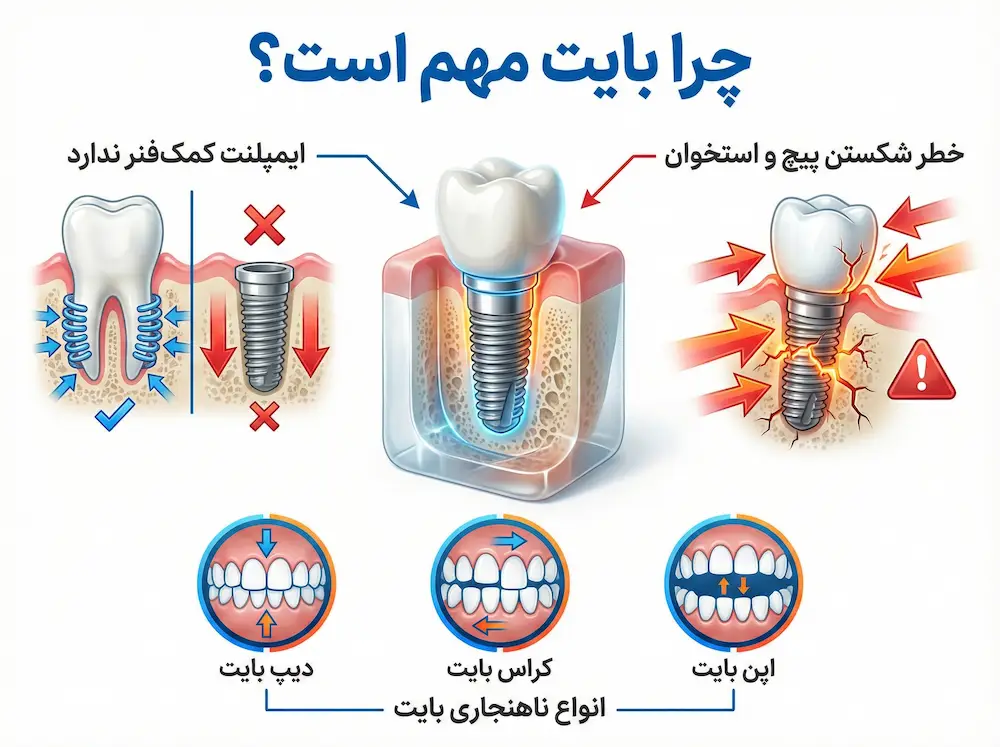

چرا؟ چون ایمپلنت برخلاف دندان طبیعی، سیستم تعلیق یا همان «لیگامان پریودنتال» را ندارد. ایمپلنت مستقیماً به استخوان جوش خورده است؛ بنابراین هر ضربه یا فشار اضافی ناشی از بایت نامناسب، بدون هیچ فیلتری مستقیماً به استخوان فک و پیچ اباتمنت وارد میشود. این یعنی اگر بایت را درست تحلیل نکنیم، حتی بهترین برندهای دنیا هم ممکن است دچار لقی پیچ، تحلیل استخوان یا شکست پروتز شوند.به همین دلیل برندهای معتبر جهان (Straumann، Nobel Biocare، Zimmer Biomet) در دستورالعملهای رسمی خود تاکید میکنند که تشخیص دقیق نوع بایت، اصلاح ناهنجاریهای اکلوزال و انتخاب طراحی مناسب فیکسچر، از مهمترین نکات در فرایند برنامهریزی درمان هستند.

اگر دندانها زودتر از موعد با هم تماس پیدا کنند (تماس زودرس)، نیروهای مخرب به جای پخش شدن، روی یک نقطه متمرکز میشوند. نتیجه؟ فشار مستقیماً به «استخوان کرستال» (لبه استخوان دور ایمپلنت) منتقل شده و باعث تحلیل رفتن آن میشود. پزشک با شناخت دقیق بایت، میتواند نیروهای عمودی (که ایمپلنت دوست دارد) و نیروهای افقی (که قاتل ایمپلنت هستند) را مدیریت کند.

۲. کراسبایت (Crossbite):

در این حالت، دندانهای بالا و پایین در مسیر صحیح روی هم قرار نمیگیرند. طبق گایدلاینهای ITI، کراسبایت خطرناکترین نیروها، یعنی «نیروهای جانبی» (Lateral Forces) را به ایمپلنت وارد میکند که عامل اصلی شکستن پیچ اباتمنت است.

۳. دیپبایت (Deep Bite):

وقتی دندانهای جلوی فک بالا بیش از حد روی دندانهای پایین میآیند. این وضعیت باعث فشارهای سنگین عمودی و تداخل در حرکات فک میشود. در اینجا خطر شکستن سرامیک روکش بسیار بالاست.

۴. اُپنبایت (Open Bite):

وقتی دندانهای جلو به هم نمیرسند. نتیجه؟ تمام فشار جویدن به دندانهای عقب (مولرها) منتقل میشود. این یعنی ایمپلنتهای عقبی زیر بار سنگینتری هستند و باید بسیار هوشمندانه انتخاب شوند.